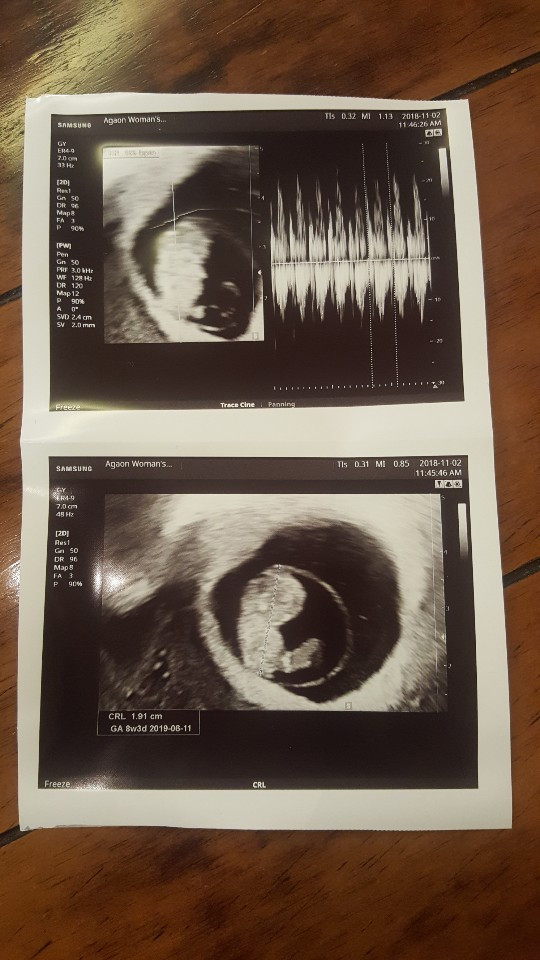

오늘 본 꼬톨이는 더 많이 커서 젤리곰 모양이 되었다. 심장도 빠르게 잘뛰고 있고 선생님께서 그동안 잘 품고 계셨네요. 라고 칭찬도 해주셨다 :)

그리고 초음파 볼 때 꼼짝꼼짝 움직이는 꼬톨이도 볼 수 있었다. 너무 귀여워.